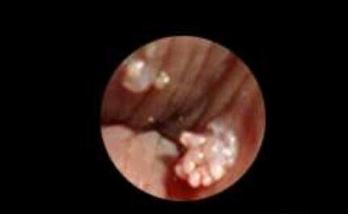

感染hpv病毒的潜伏期大概为2-3个月,在X生活后,发现自己的私处有长异样的疣体,初期是如图所示,米粒大小的丘疹,在短时间内会增大,互相融合,呈菜花状、鸡冠状的柔软疣体,容易破溃出血,如果感染还会有恶臭散出,一点要尽快治疗。

低危黏膜型HPV病毒感染以后,就是千万人唾弃的尖锐湿疣。在低危型HPV病毒里面,最常见的导致尖锐湿疣的罪魁祸首就是HPV6和11,而尖锐湿疣发生的常见部位是在外阴、肛门、yin道、宫颈、yin茎、gui头、尿道口。

在这里妖塔需要再次跟大家讲述一下尖锐湿疣和假性湿疣的区别,前面咱们说了尖锐湿疣的好发部位,典型的尖锐湿疣是非对称随机分布的,而且一般呈单发或多发乳头状、菜花状肿物。

这是女性早期的小疣体,多长在YD、阴唇、肛门、宫颈内或者是尿道口,早期就是淡红色、柔软的细小丘疹,因为面积不大,所以很容易被忽视,还会感觉外阴瘙痒,疼痛,疣体很脆容易出血……